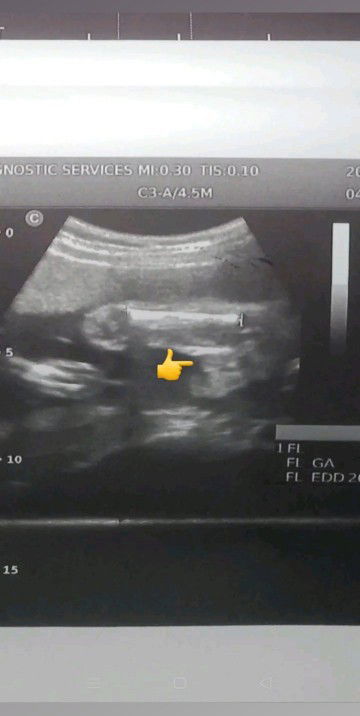

Anopo sa tingen nyo mga mi girl or boy😅😊💖dipa dw po Kase sure kung girl eh kaya need ulitin pag 8 moths na dw po nung sabado papo yang ultrasound ko 23 weeks & 4 days napo ako now #advicepls

labo ung pic pero prnag girl kasi mukhang burger.

yan po mi hehe